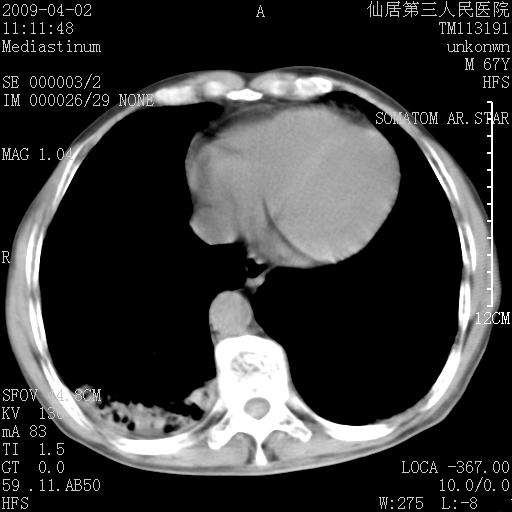

患者老年男性,乏力畏寒来诊,摄胸片示右下肺感染性病变,抗炎两周后复查胸片,无好转有进展。

后做ct平扫表现如下:

病灶呈蜂窝征,纵隔多个淋巴结肿大;肺泡癌需考虑

我认为普通的感染应该可以除外,间质性肺炎可能性较大,但如何解释纵膈的淋巴结肿大呢